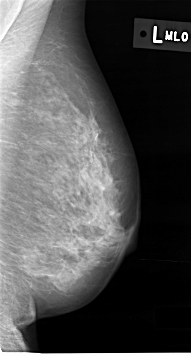

C_0012_1.LEFT_MLO

LEFT_MLO LINES 4616 PIXELS_PER_LINE 2472 BITS_PER_PIXEL 12 RESOLUTION 50 NON_OVERLAY